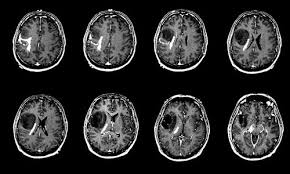

قند تومورهای مغزی را تغذیه کرده و آنها را تهاجمی‌تر می‌کند

دانشمندان به شواهدی دست یافته‌اند که نشان می دهد قند باعث تحریک سلول‌های سرطانی شده و آنها را تهاجمی‌تر می‌کند.

بنا بر گزارشی که پس از ۹ سال تحقیق در آزمایشگاههای بلژیک منتشر شد، مصرف بیش از اندازۀ شکر باعث می‌شود که «چرخۀ حیرت‌انگیزی» در سلول‌های سرطانی بوجود آید و در این چرخه گلوکز باعث فعال‌تر شدن سریع‌تر پروئین‌هایی به نام «راس» (Ras proteins) شود (نوعی از پروئین که اغلب در سلول‌های جهش یافته و بیش از حد فعالِ سرطانی وجود دارد) و به این ترتیب تولید و تکثیر سلول‌های سرطانی ادامه یابد.